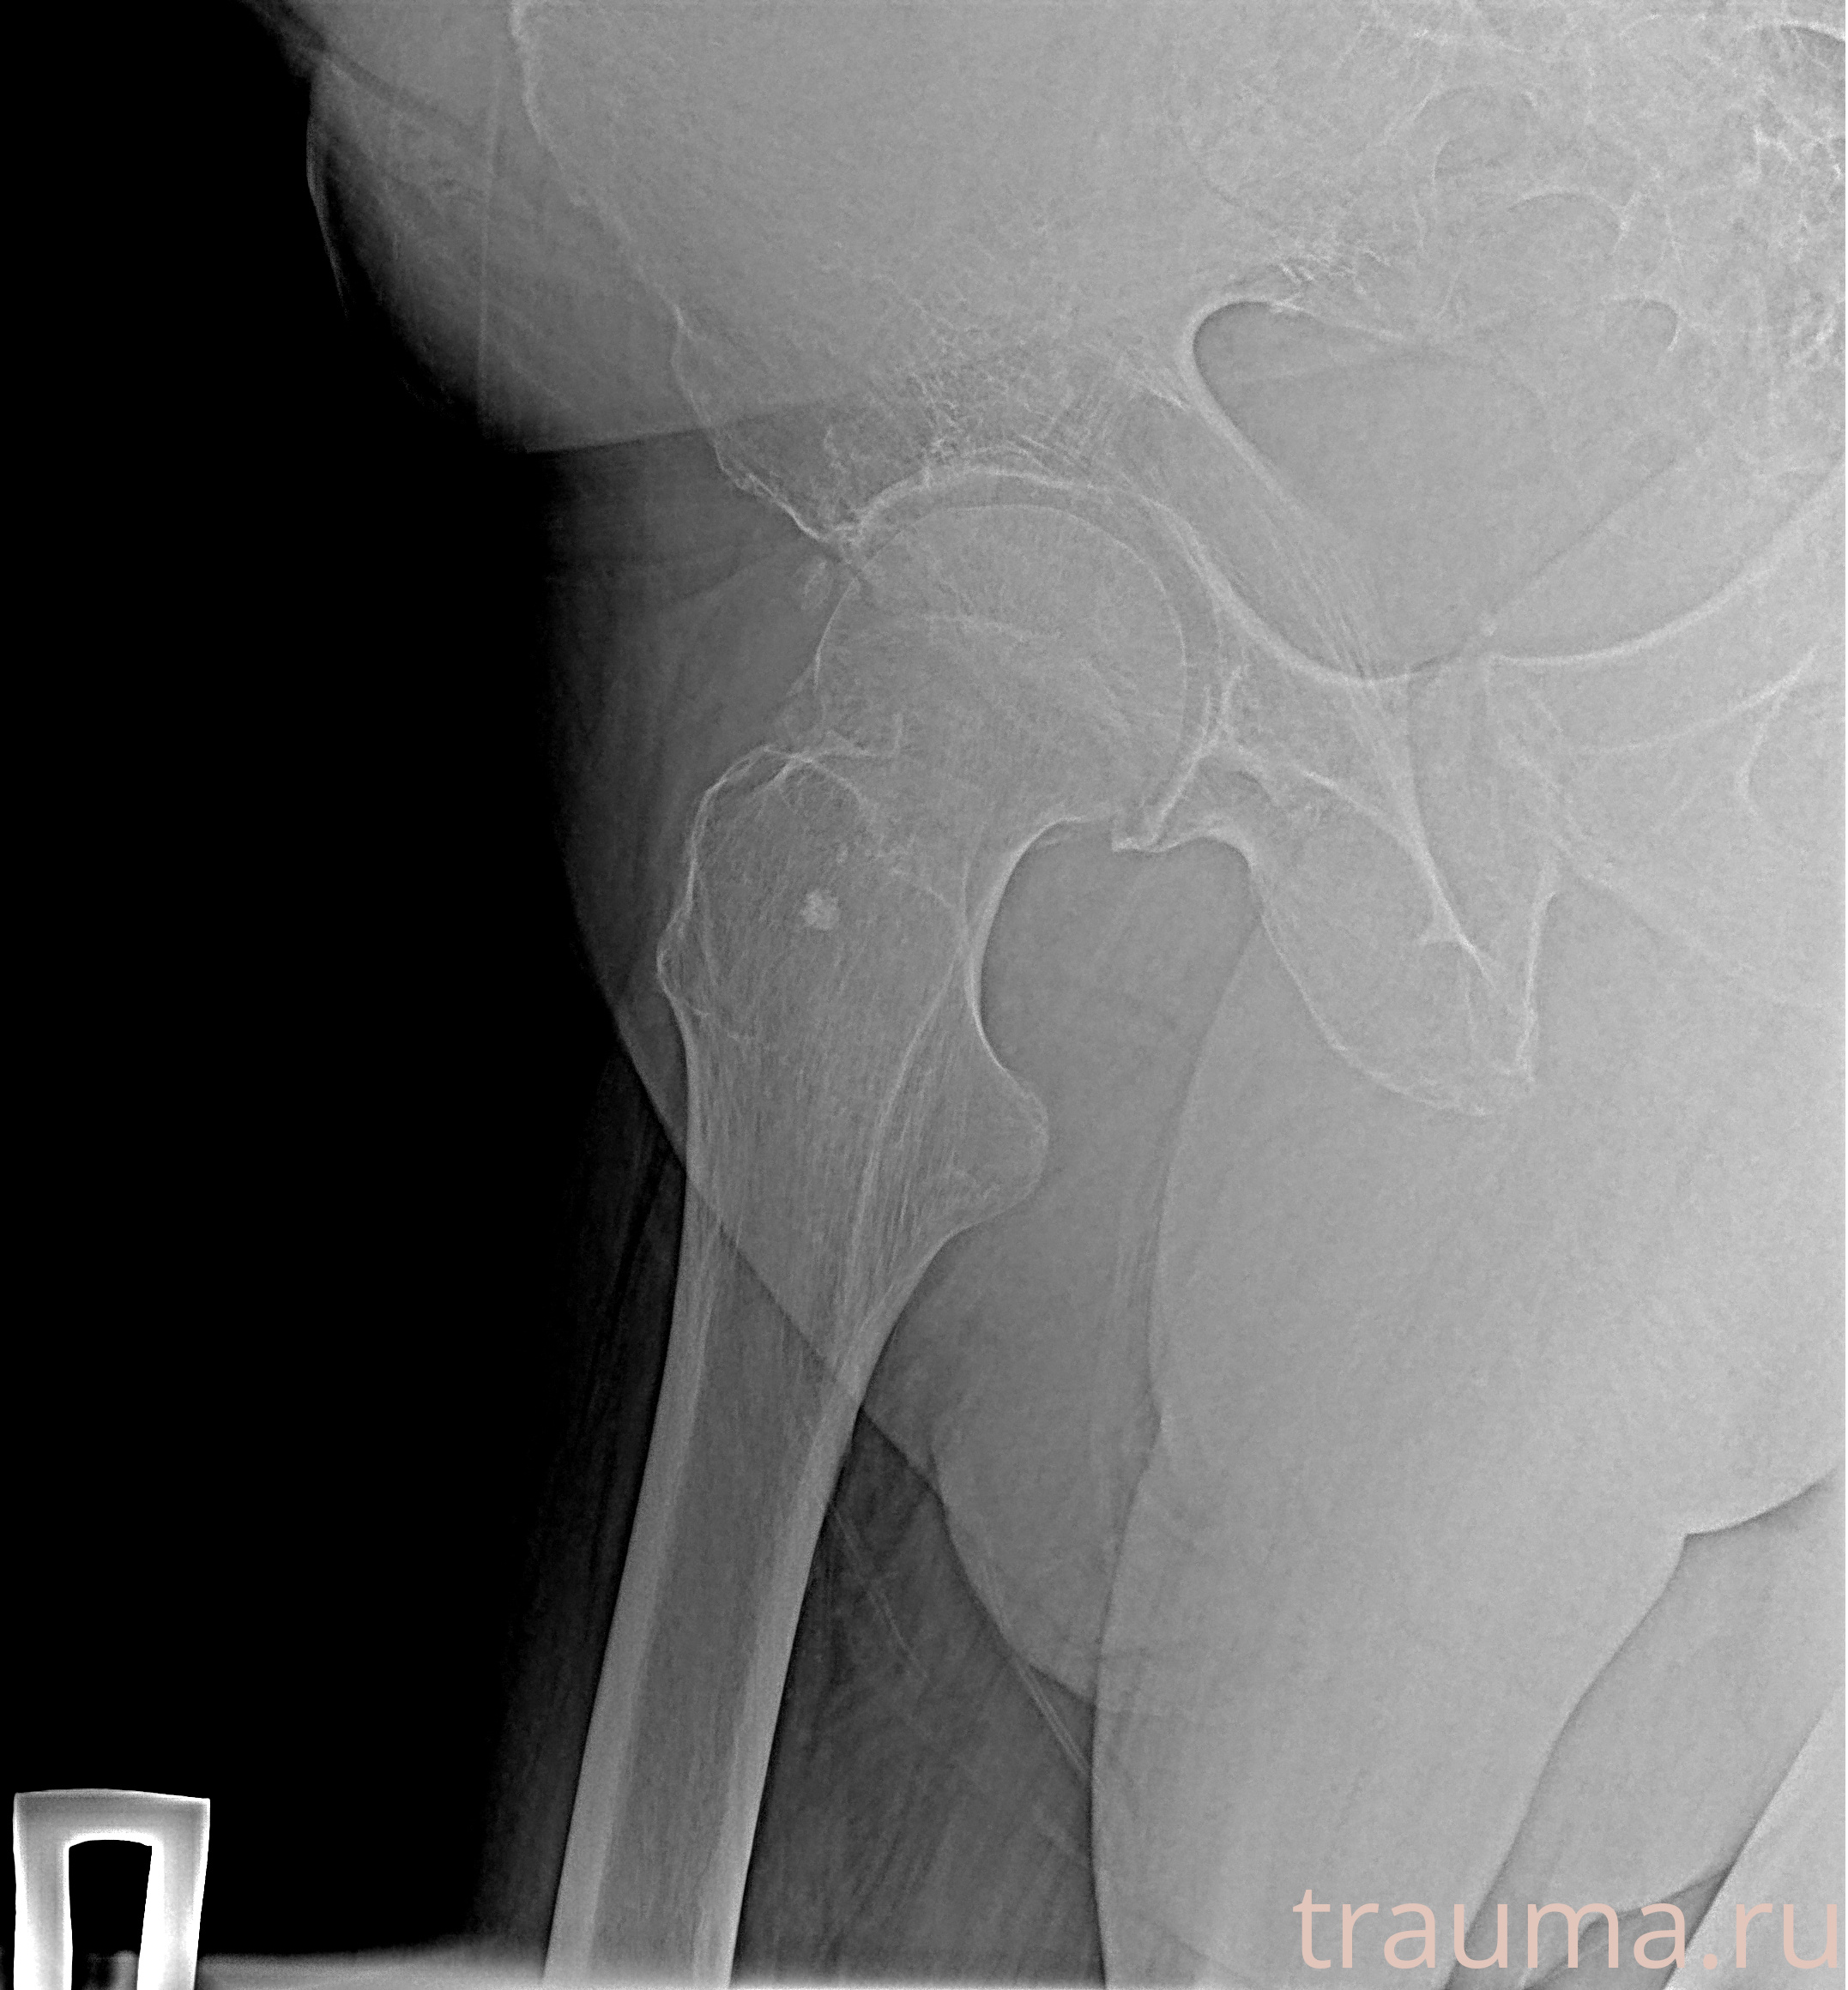

Рентгенограммы

Рентген на дому: по вашему адресу приезжает врач-рентгенолог, травматолог-ортопед с мобильным рентгеновским аппаратом, проводит диагностику травмы или заболевания, делает необходимые рентгенограммы, дает рекомендации по дальнейшему лечению. Получить качественные снимки в домашних условиях возможно благодаря уникальной методике, разработанной МосРентген Центром для института  Склифосовского